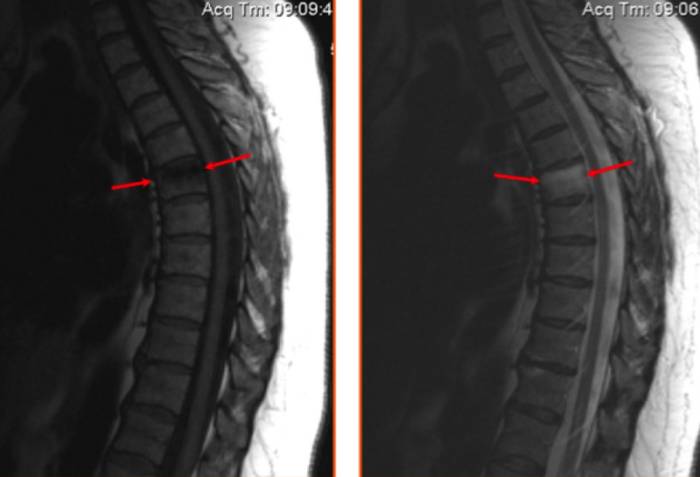

На МР-изображении стрелками показан ушиб шестого грудного позвонка (визуализируется отек костных структур без деформации тела позвонка)